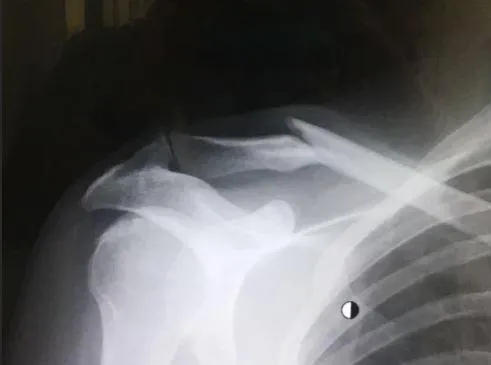

Kết quả chụp X-quang của Porte cho thấy tổn thương ở cổ.

Kết quả chụp phim cho thấy Porte bị gãy xương đòn phải, cổ và những vết xước trên mặt. Ở giai đoạn này, Porte chưa cần phải phẫu thuật. Việc có phẫu thuật hay không sẽ được đội ngũ bác sĩ đánh giá và có kết luận vào ngày mai. Có thể khẳng định Porte đủ sức khỏe để về nhà”.